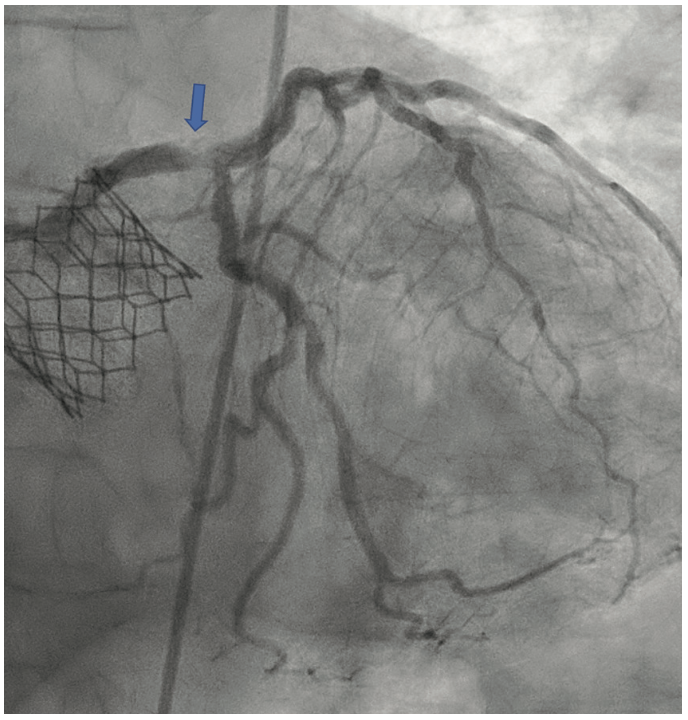

The patient’s electrocardiogram showed sinus rhythm with left bundle branch block and echocardiography demonstrated a normal left ventricular ejection fraction with a transvalvular aortic mean gradient of 10 mmHg. On further evaluation, his nuclear stress test showed severe anterior ischemia. A review of his previous angiograms demonstrated an underexpanded stent in the distal LM that was potentially constrained by a circumferential calcific lesion (Figure 1). Intravascular ultrasound (IVUS) and atherectomy were not utilized during the index procedure. The patient underwent cardiac catheterization via the right femoral approach, which demonstrated severe in-stent restenosis (ISR) of the distal LM due to an underexpanded/undersized stent (Figure 2), confirmed on assessment of the non-contrast chest imaging and IVUS, with a minimum stent area (MSA) of 4 mm2 (Figure 3). Given the patient was not a surgical candidate, further percutaneous management was elected as the best management strategy since the patient had refractory angina despite medical therapy. Mechanical support with large-bore access was not feasible, given the vascular disease in his lower extremities had worsened, and with severe carotid disease, the patient was not a candidate for axillary large-bore devices. He was pre-treated with aspirin and clopidogrel before the PCI.

The LM was engaged with a 7 French (F) XB 3.5 guide catheter (Cordis Corporation). A workhorse coronary wire was advanced to the distal left anterior descending (LAD) coronary artery and another workhorse wire was advanced to the distal obtuse marginal. Serial inflations with 3.5 mm x 20 mm NC balloon were performed at 20 atmospheres (atm) in the distal LM. A kissing balloon inflation (KBI) was done using two 3.5 mm x 12 mm NC balloons at 12 atm. The ostium of the left circumflex (LCX) and distal LM was further prepared using a 4 mm x 10 mm Wolverine cutting balloon (Boston Scientific) at 12 atm. The distal LM lesion did not yield, despite multiple balloon inflations. Hence, a 4 mm x 12 mm IVL balloon (Shockwave Medical) was used at 4 atm for 40 pulses. These inflations had to be supported with intravenous norepinephrine boluses. Later, a 4 mm x 12 mm NC balloon was used and the result showed adequate expansion across the LCX ostium. A double-kissing culotte was completed and the proximal LAD was stented with a 3.5 mm x 24 mm Synergy Megatron (Boston Scientific) at 12 atm. Proximal optimization technique (POT) was performed using a 5 mm x 12 mm NC balloon at 20 atm. The LCX was re-crossed using another workhorse wire and the jailed LCX wire was removed. The side struts were opened using a 2 mm x 12 mm semi-compliant balloon, followed by KBI with two 4 mm x 12 mm NC balloons at 12 atm. Re-POT was done using 5.5 mm x 12 mm NC balloon at 22 atm with an excellent result (Figure 4). The final IVUS demonstrated a MSA of 11 mm2 in the distal LM, and 9 mm2 MSA was attained in the ostium of the LAD and LCX (Figure 5). Total contrast used in the procedure was 30 mL, as IVUS was used significantly during the PCI in view of the complex lesion, as well as the patient’s pre-existing renal impairment. He was discharged the next day after post PCI hydration with dual antiplatelet therapy for six months and he had no change in creatinine at the end of one week. At four weeks, the patient is well without any angina and is asymptomatic from a cardiac perspective.